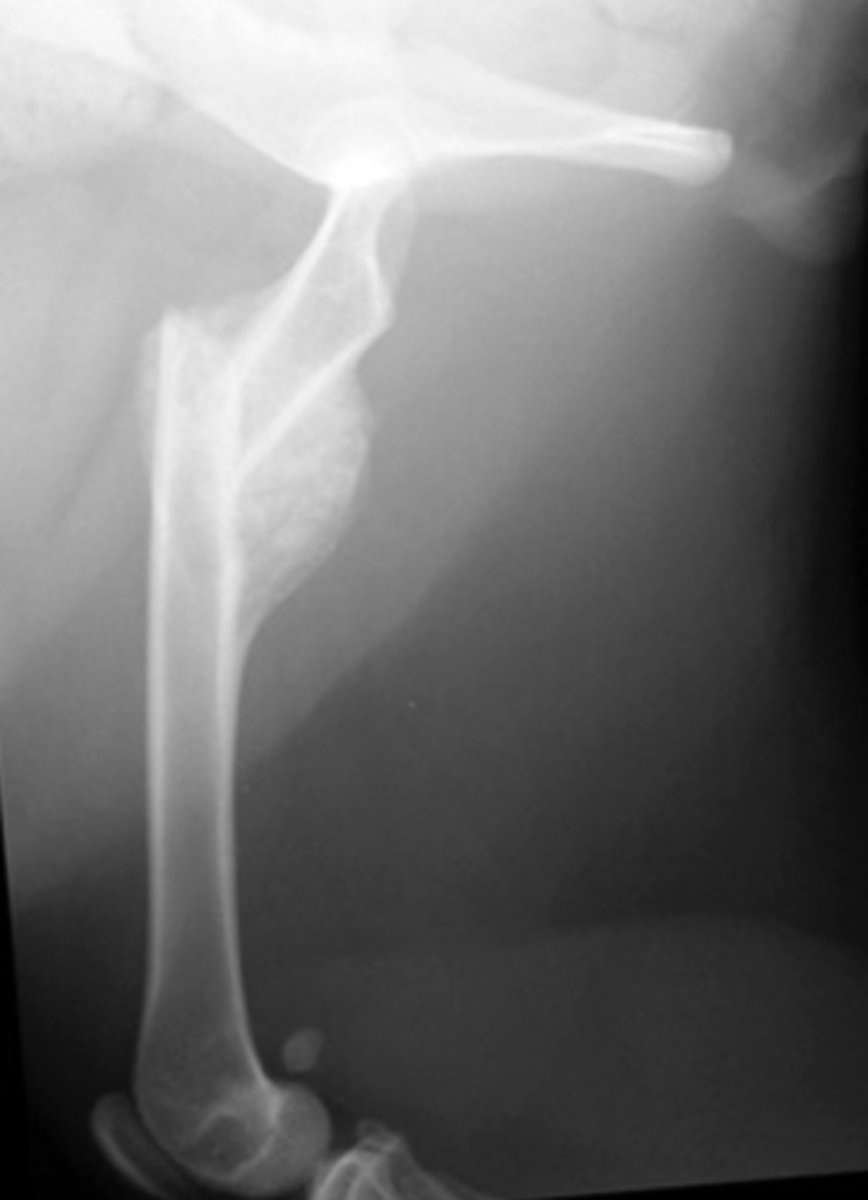

What is this an example of?

Malunion

What is a malunion?

the healing of a bone in a nonanatomic position